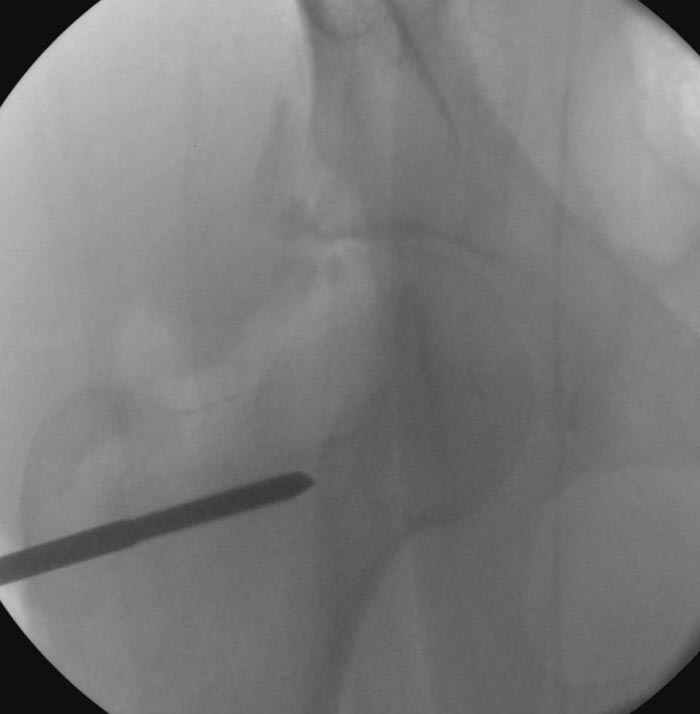

5:24 Рентгенограмма таза, вызывают врача ортопеда (снимок N1), его диагноз: закрытый переломо-вывих правого тазабедренного сустава, получает добро на закрытую репозицию в приемном отделении

5:38 Дважды неудачная попытка закрытой репозиции в приемном отделении

N 2

6:20 ответстенный врач принимает решение о репозиции в условиях операционной, предупреждаются родственники и больной, что при неудачной закрытой репозиции, о возможности открытой репозиции и фиксации задней стенки вертлужной впадины.

7:30 начало операции, больной на спине, попытка репозиции после анестезии N3, укладка больного на боку, доступ Kocher- Langenbeck, состояние седалищнего нерва около 2.5см кровоподтек, через joistick головка бедра приподнята, освобовождение сустава, фрагмент заднего края более 3х4 см репонирован на свое место. После промывания

сустава, репозиция вывиха (N4), фиксация фрагмента 2.7(4) мм шурупами и допольнительно реконструктивной пластиной на 8 дырок, фиксация 3.5мм шурупами проксимально и дистально.

Интраоперционные N5 косая запирательная и N6 подвздошный снимок